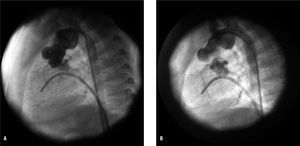

En 8 (57%) de los 14 pacientes se observó obstrucción significativa en el neoarco aórtico (gradiente pico ventrículo derecho-aorta descendente ≥ 15 mmHg, con imagen angiográfica de reducción del calibre > 50%). No encontramos diferencia significativa en la incidencia de recoartación entre los pacientes en los que se había utilizado tejido heterólogo para la reconstrucción del arco aórtico (5/9) y los que no (3/5). El tiempo transcurrido entre la cirugía Norwood I y el diagnóstico de recoartación fue de 9,5 meses (4 meses-2,5 años). Se realizaron 9 angioplastias a 7 pacientes (en uno de ellos se desestimó la angioplastia por inestabilidad hemodinámica y fue remitido a cirugía), utilizando la arteria femoral (vía retrógrada) en 7 y la vía venosa femoral (vía retrógrada) en 2 (por estenosis de arteria femoral). Se consiguió angioplastia inicialmente efectiva en 6/7 pacientes (85%) (fig. 1), pero 2 presentaron en el seguimiento nueva recoartación y fueron sometidos a una segunda angioplastia, que fue efectiva en uno de ellos; se derivó al otro a cirugía. Las características de los pacientes en los que se realizó angioplastia de recoartación, así como los datos angiohemodinámicos, se resumen en la tabla 1.

Fig. 1. A: recoartación en paciente de 4 meses y 3,3 kg de peso (técnica quirúrgica: reconstrucción de arco sin tejido heterólogo), con máximo gradiente de 35 mmHg y diámetro de la lesión de 2,8 mm. B: tras la angioplastia con balón Tyshak mini (Numed®) de 7 mm, gradiente de 0 mmHg y diámetro de la estenosis de 5 mm.